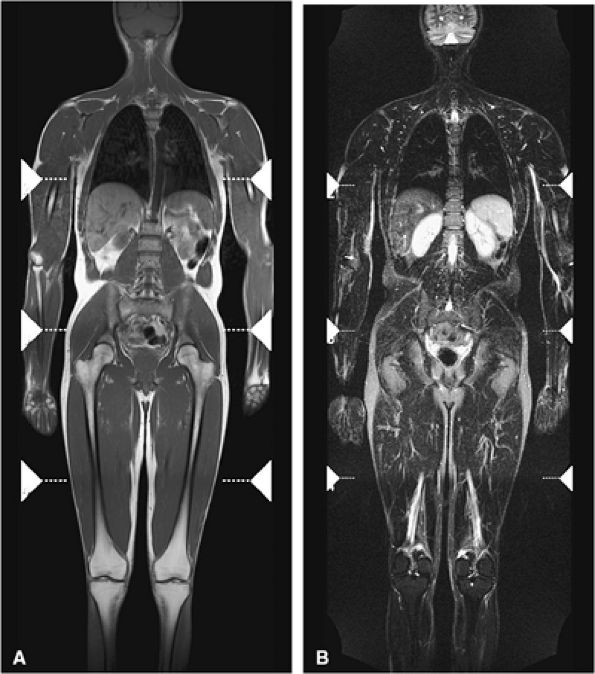

FIGURE 13.8 ● Whole-body MR imaging using coronal T1-weighted (A) and coronal STIR (B) sequences. Whole-body MRI is a sensitive and fast technique for evaluating the entire skeleton for abnormalities.

comparing whole-body MR imaging using a rolling table platform with bone scintigraphy, excellent correlation between the two modalities in lesion detection has been demonstrated, and the examination time was 40 minutes or less.35